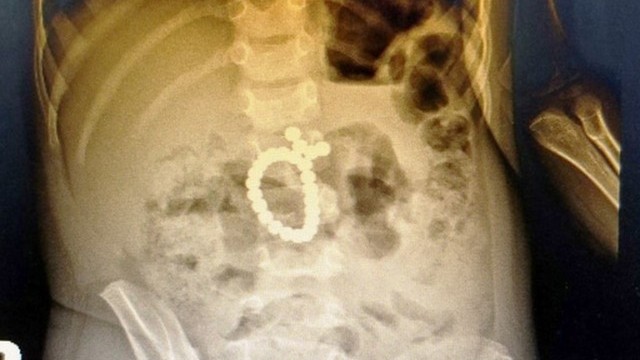

Nghệ An: Cứu bệnh nhân nhi nuốt 25 viên bi nam châm, thủng ruột và tá tràng

Hướng dẫn nuôi dạy con -  07/01/2022

Các viên bi nam châm do trẻ nuốt vào.   Ngay sau khi tiếp nhận, qua các xét nghiệm và X-quang ổ bụng bệnh nhi, các bác sĩ đã phát hiện bệnh...